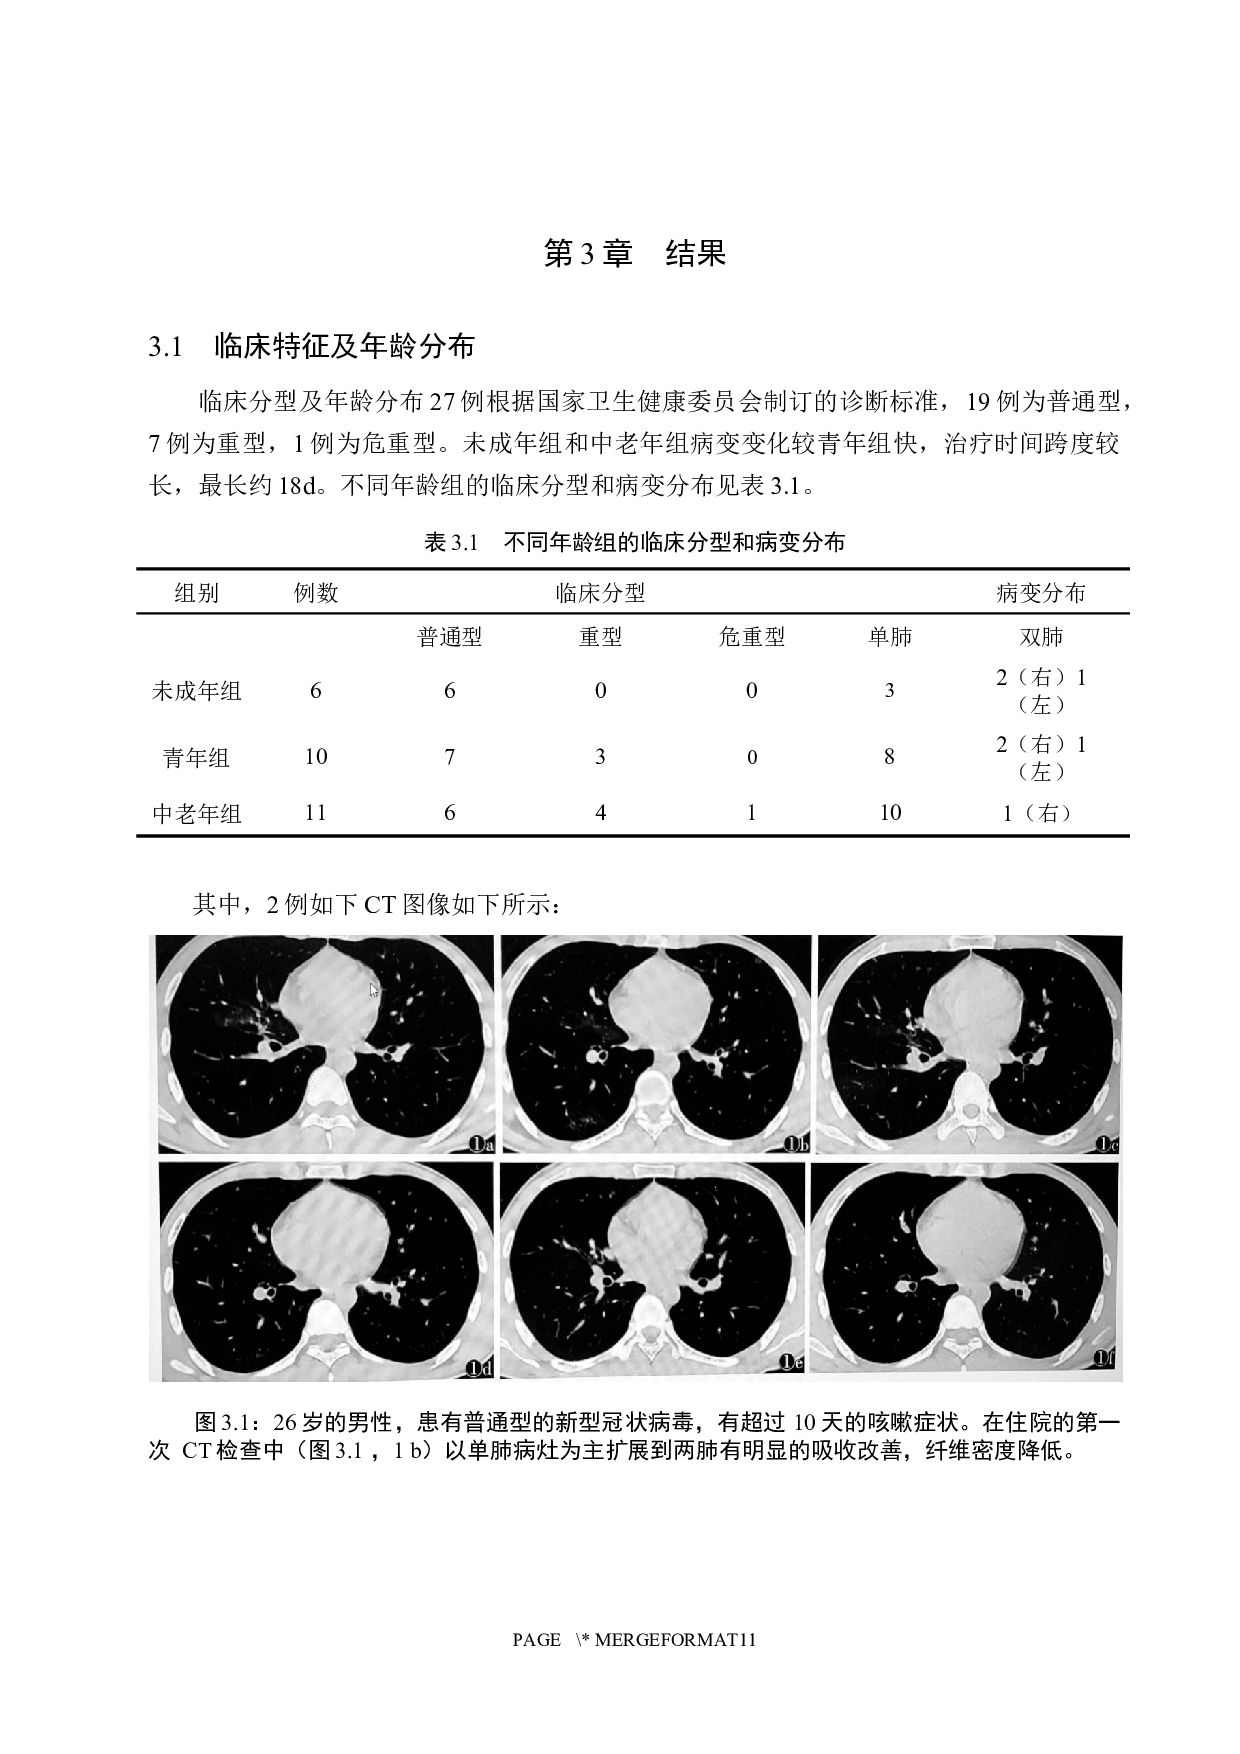

摘 要 目的 : 探讨 CT 检查 技术 在 病毒 性 肺炎的 应用价值 。 方法: 选取 27 例经临床诊断和核酸检测确诊 为 COVID-19 的病例,通过了解 患者的 基本信息和病情 进行回顾性分析 ,将所有的 首次胸部 CT 检查结果与 15 例 41 次 CT 复查 结果 进行比较研究。 结果: 研究发现,患有此病的人 CT 表现通常会在双肺中出现多个磨玻璃样或浸润性影像,在极端情况下,还会导致肺实质的改变。在本文 27 例 临床患者 中, 1 9 例为普通型, 7 例为重型, 1 例为危重型。重型 中 有 2 例表现为 肺部磨玻璃影 ,达到出院标准 后肺部的 磨玻